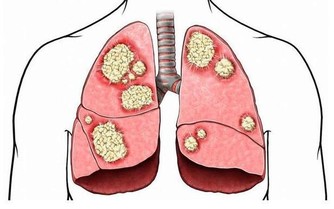

別的一些疾病也會合併口腔潰瘍,比如萊特爾綜合徵、白塞氏病、腫瘤等等疾病會伴發口腔潰瘍。

6. 一些嚴重的疾病,例如白塞氏病和口腔內的惡性腫瘤,此時往往遷延不愈,且可能伴隨全身其它症狀。